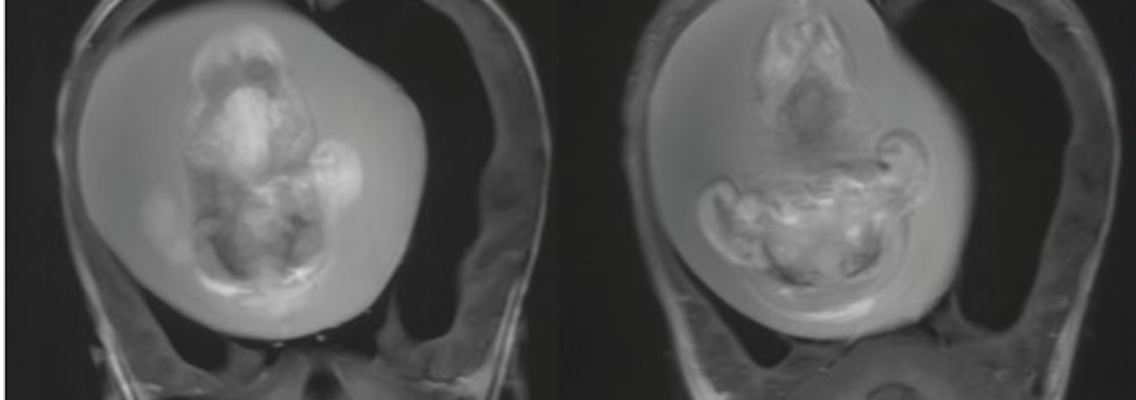

Für Ärztinnen und Ärzte einer Klinik in der indischen Hauptstadt Neu-Delhi ist es ein besonders herausfordernder Eingriff: Einem Jugendlichen ragen Teile seines parasitären Zwillings aus dem Bauch. Das Phänomen ist äußerst selten - entsprechend anspruchsvoll gestaltet sich die Operation.

Ärzte in der indischen Hauptstadt Neu-Delhi haben einem Teenager einen parasitären Zwilling entfernt, der an seinem Bauch angewachsen war. Dem 17-Jährigen wuchsen ein zusätzliches Paar Beine sowie ein Gesäß und äußere Genitalien, wie die BBC berichtet. Demnach waren die Teile seines parasitären Zwillings insgesamt 15 Kilogramm schwer und ragten aus seinem Bauch heraus. Durch eine Arterie in der Brust wurden sie mit Blut versorgt. Die rund zweistündige Operation im AIIMS-Krankenhaus verlief dem Bericht zufolge erfolgreich - stellte die behandelnden Ärzte jedoch vor eine große Herausforderung.

Die Operation wurde demnach in zwei Schritten durchgeführt: Zunächst wurden die Teile des parasitären Zwillings, anschließend die zystische Masse aus den umliegenden Organen entfernt. "Ein Geflecht aus gemeinsamen Blutgefäßen, Nerven und Geweben musste getrennt werden. Es musste darauf geachtet werden, dass keines der Organe oder Gewebe des Wirts beschädigt wurde", sagte Krishna.